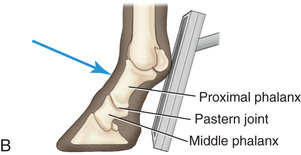

The main indications for radiography of the middle and proximal phalanx and proximal interphalangeal joint are lameness localized with clinical examination or diagnostic analgesia and penetrating wounds. Specific views of this area are best obtained with the horse bearing weight squarely on all four limbs.

The lateromedial view of the pastern provides information on the integrity of the foot axis and the bones and joints in the digit.

The dorsopalmar (D30-45Pr-PaDiO) view of the pastern is a standard view to evaluate the causes of forelimb and hind limb lameness. Additional views of the opposite limb are indicated in patients less than 9 months of age. Comparison studies permit evaluation of physeal closure.2

Oblique views of the pastern are as follows (Fig. 24.20):